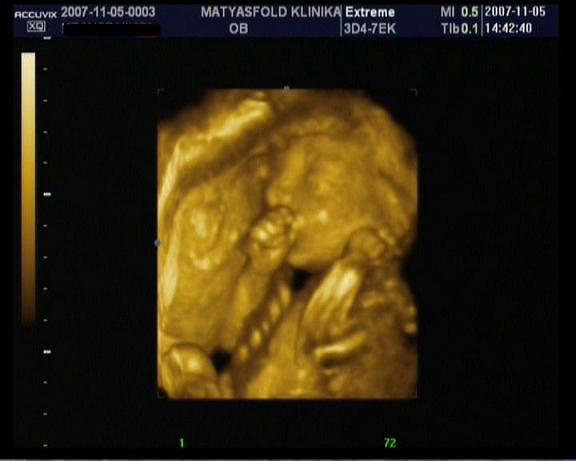

a 7ik héttől már látható a szívcső lüktetése, 8ik héttől a gerincoszlop és már akár testmozgások is láthatók! Ez nem jelenti azt, hogy feltétlenül mozogni is fog az uh alatt, valamikor ő is pihen!

Persze ezekhez szakértő szem szükséges, tehát az orvos mindent látni fog, és el fog mondani!!